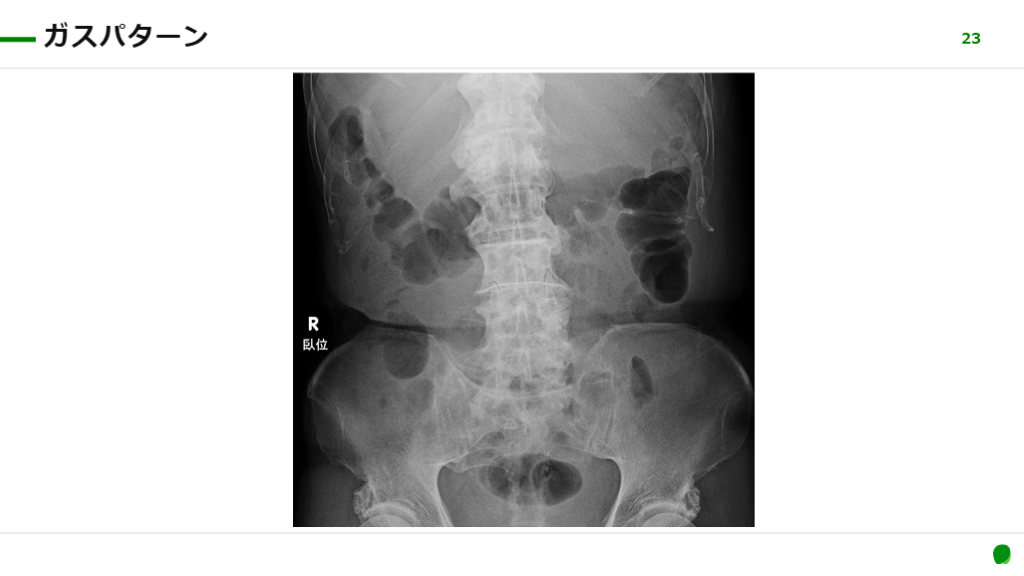

ガスパターンの評価と正常値

#21.

ガスパターン 21 全体のガスパターン free air 軟部組織 石灰化病変 骨 XXXXX XXXXX

#22.

22 3)稲岡勉,他.腹部単純X線撮影.medicina.41(12):2004. ガスパターン ・まずは小腸と結腸の判別がつけられるようにしよう! ・〇〇signとか基準は覚えられなくても調べればOK.パッと見て小腸大腸の異常が分かれば上等. 画像での「位置」と「皺」をみる. ポイント 回腸のairは小さな丸. 空腸のKerckringヒダは完全に横断することが多い. 結腸のハウストラは完全に横断しないことが多い. 注意点 文献3より引用

#23.

23 ガスパターン

#24.

24 ガスパターン 結腸 ハウストラ (普通は完全に横断しない) 空腸 Kerckringヒダ (細かいヒダが完全に横断する) 回腸 小さな〇

#25.

ガスパターン ・正常の基準を知っておこう. ・基準があることを知っていればいざというときに調べられる. 25 小腸(正常値) ・長径<3cm ・壁の厚さ<3mm ・液面形成<3個 大腸(正常値) ・長径<6cm ・回盲部径<9cm 「3の法則」